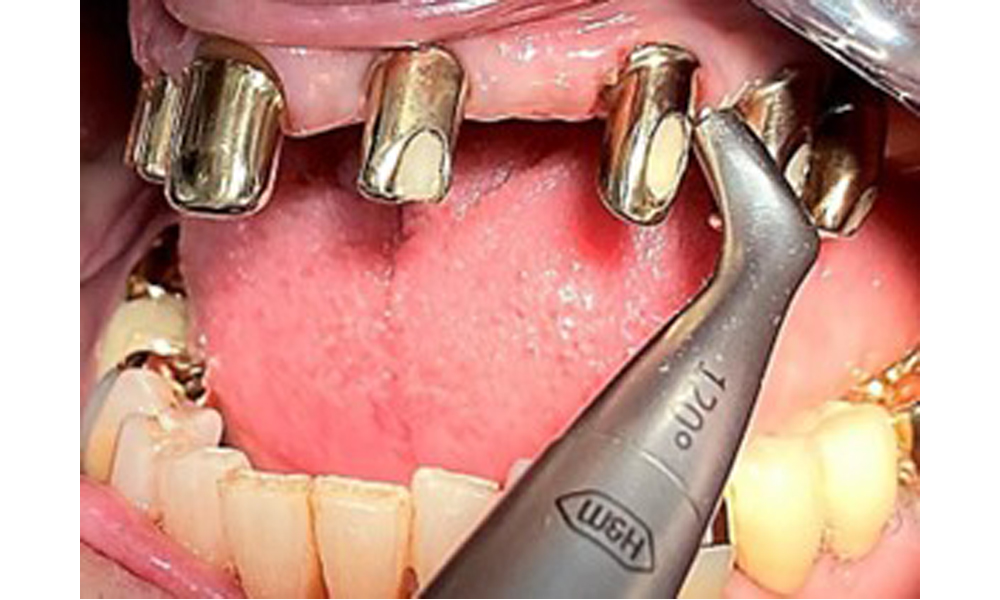

Die Patientin wurde vor über 25 Jahren mit einer kombinierten herausnehmbare Implantat-Teleskopprothese im Oberkiefer versorgt (Abb. 1, Abb. 2, Abb. 3) und ist sehr glücklich über ihren Zahnersatz. Im Unterkiefer hat die Patientin einen suffizienten festsitzenden Zahnersatz. (Abb. 4)

Der dentale Befund stellt sich wie folgt dar: Kombinierte herausnehmbare Implantat- und zahngetragene Teleskoparbeit auf Implantaten 15, 13, 21, 23, 24, 25 und Zahn 11 (Abb. 1, Abb. 2, Abb. 3). Im Unterkiefer ist die Patientin mit einem festsitzenden Zahnersatz versorgt. 37–34 sowie 45–47 haben suffiziente Brücken (Abb. 4). Kronenränder sind intakt, aktive kariöse Läsionen sind nicht vorhanden. An Zahn 43 zeigt sich eine Compositefüllung mit Randspalt. Im Unterkiefer liegen Rezessionen mit freiliegender Wurzeloberfläche zwischen 1 – 3 mm vor. Dies trifft auch für 11 zu.